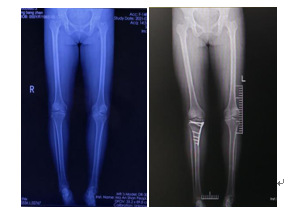

病例1:55歲的女性李某,在關(guān)節(jié)骨科行“脛骨高位截骨術(shù)”治療膝關(guān)節(jié)骨關(guān)節(jié)炎,術(shù)后患者非常滿意。